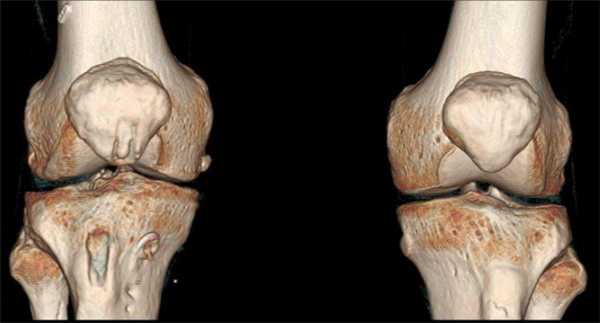

КТ коленных суставов (трехмерная реконструкция)